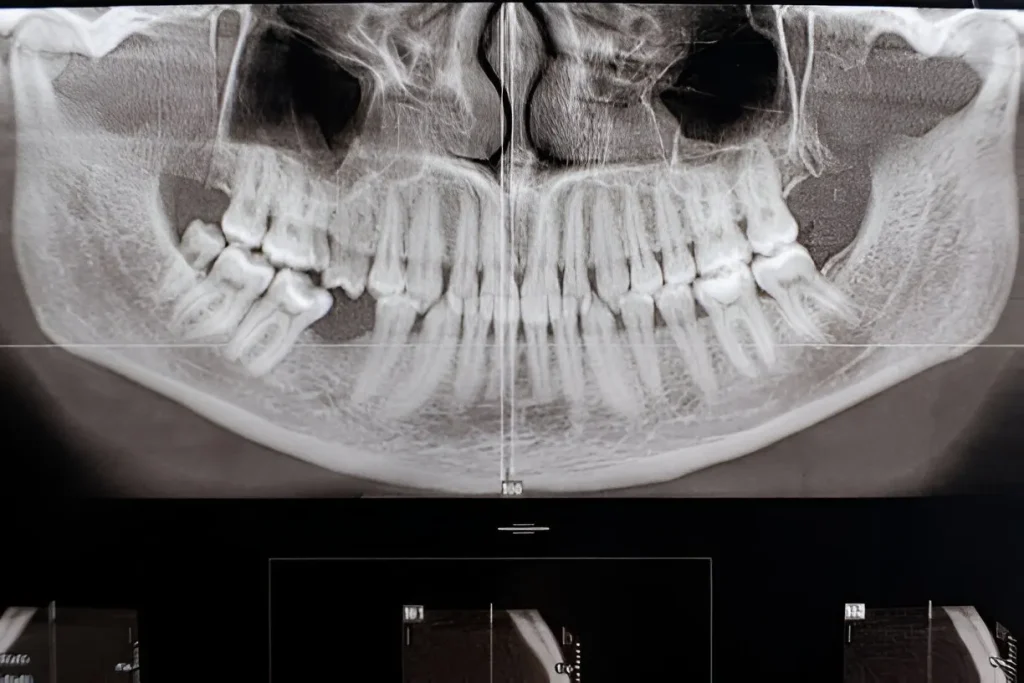

CT Temporomandibular Joint in Navi Mumbai | Henotic Diagnostics

At Henotic Diagnostics, we offer advanced CT Temporomandibular Joint (TMJ) scan in Kharghar, providing precise imaging to evaluate jaw pain, limited movement, or suspected joint disorders. Since CT TMJ captures detailed bone structures, it helps doctors diagnose arthritis, fractures, or abnormalities effectively. Moreover, our expert radiologists ensure accurate reports, while modern scanners minimize radiation exposure. Consequently, patients receive safe, reliable, and quick results. Therefore, if you need a CT Temporomandibular Joint Near You, Henotic Diagnostics is your trusted choice.